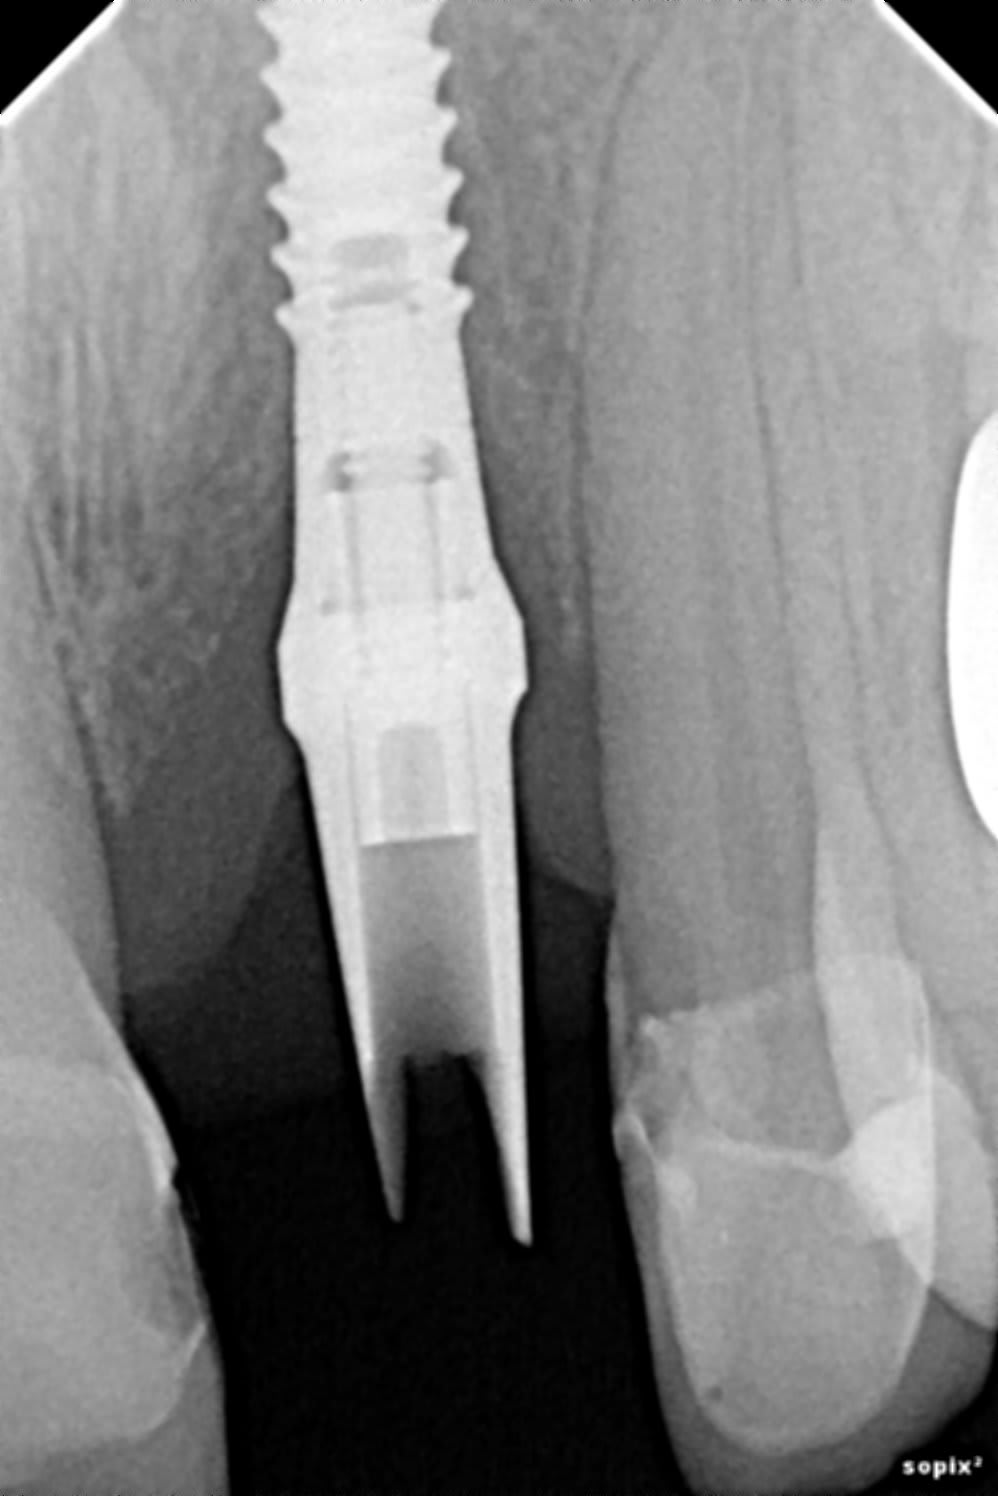

J'ai une patiente à qui on a posé un implant + greffe en place de 21, puis la CCM avec le pilier.

Comment puis-je améliorer le contour gingival ? Conjonctif enfoui en gardant le pilier (ou mettre un pilier angulé) ? Puis-je garder la CCM (si je ne change pas le pilier) en provisoire le temps que ça cicatrise ?

J'ai réalisé la couronne sur implant oui. Je savais que ça allait être compliqué, j'aurais dû demandé de faire le collet rose.

L'implant a été posé par un confrère qui gère plutôt bien mais il y avait une grosse résorption.